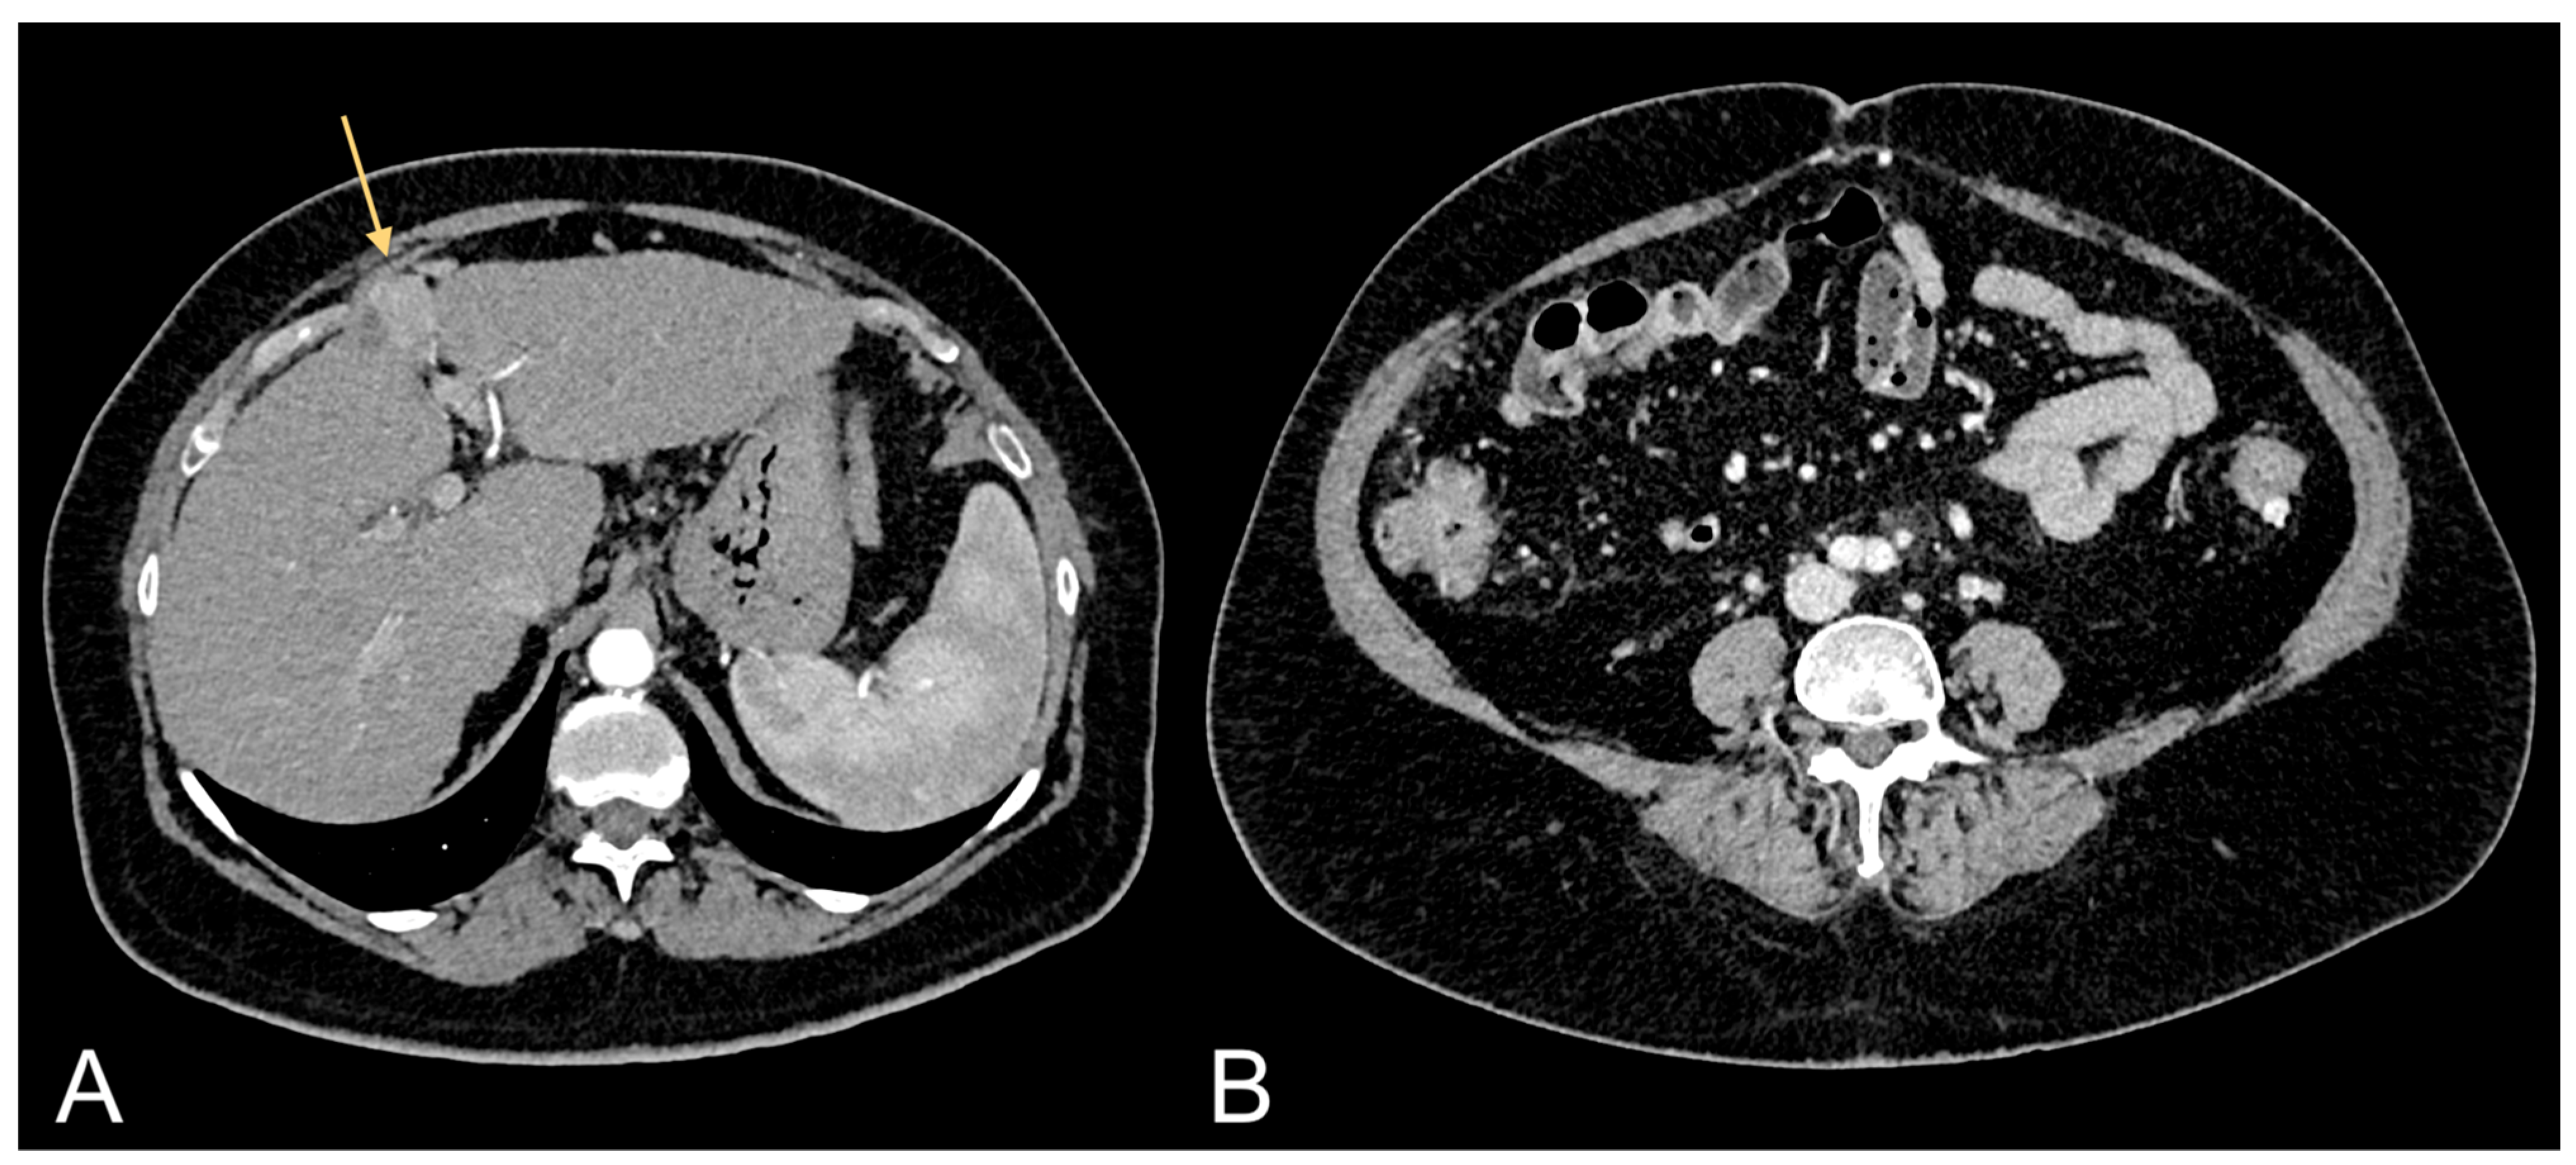

Figure 2.

Contrast-enhanced CT images of a 69-year-old female patient showing HCC in cirrhotic liver (light orange arrow in (A)) and relative excessive amount of VAT (B).